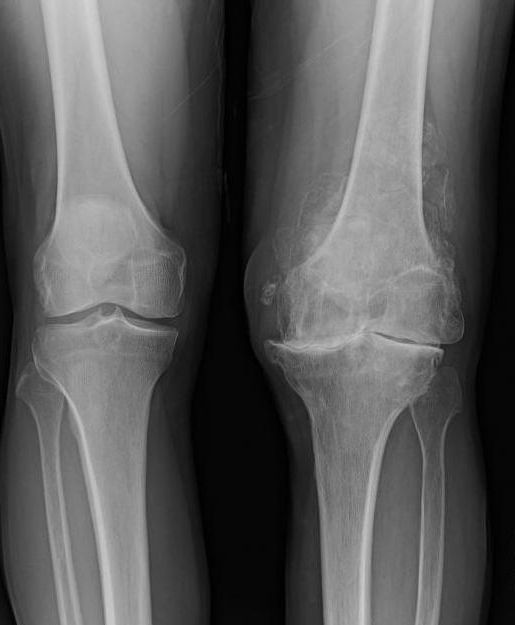

- Рентген сустава.

В большинстве случаев для диагностики достаточно проведения пункции, называемой артроцентезом. Взятая из сустава жидкость исследуется и назначается лечение. Для лиц, у которых колено было травмировано, подагра коленного сустава выявляется при помощи рентгена.

Рентгенологическое обследование при подагре

Как подтвердить наличие такого заболевания, как подагрический артрит коленного сустава? Рентген по праву считается одним из самых доступных и информативных методов. На снимке врач может отметить появление изменений в кортикальных слоях кости. На эпифизе кости образуются округлые дефекты со склеротической каймой.

К прочим признакам можно отнести расширение тени от мягких тканей сустава на снимке, что связано с отложением кристаллов. Наблюдается и сужение суставной щели.